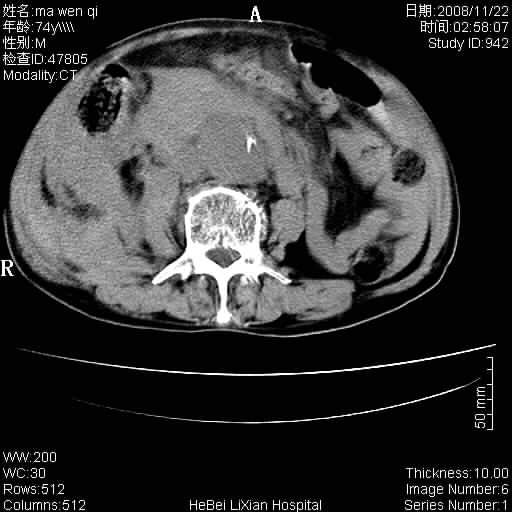

患者男 74岁.突然昏迷,休克6小时.血压70/30,头颅ct未见异常,既往体健.

补充病史,保留导尿10小时,尿袋内只有少许尿液,患者于住院后15小时后去世.

1)考虑双侧髂动脉瘤并右侧动脉瘤破裂出血,右侧腹膜后及腹腔积血。2)双侧腹股沟疝。

1)考虑,腹主动脉、双侧髂动脉夹层动脉瘤破裂伴右侧腹膜后及腹腔积血。2)双侧腹股沟疝。

1)考虑胸、腹主动脉、双侧髂动脉瘤并右侧动脉瘤破裂出血,右侧腹膜后及腹腔积血。2)双侧腹股沟疝。